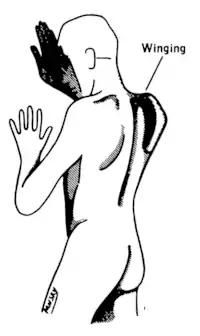

Shoulder elevation and head-turning (XI)

The accessory nerve (XI) supplies the sternocleidomastoid and trapezius muscles.[16]

Damage to the accessory nerve (XI) will lead to weakness in the trapezius muscle on the same side as the damage. The trapezius lifts the shoulder when shrugging, so the affected shoulder will not be able to shrug and the shoulder blade (scapula) will protrude into a winged position.[3] Depending on the location of the lesion there may also be weakness present in the sternocleidomastoid muscle, which acts to turn the head so that the face points to the opposite side.[16]

A cranial nerve exam starts with observation of the patient, as some cranial nerve lesions may affect the symmetry of the eyes or face.[16] Vision may be tested by examining the visual fields, or by examining the retina with an ophthalmoscope, using a process known as funduscopy. Visual field testing may be used to pin-point structural lesions in the optic nerve, or further along the visual pathways.[17] Eye movement is tested and abnormalities such as nystagmus are observed for. The sensation of the face is tested, and patients are asked to perform different facial movements, such as puffing out of the cheeks. Hearing is checked by voice and tuning forks. The patient's uvula is examined. After performing a shrug and head turn, the patient's tongue function is assessed by various tongue movements.[16]